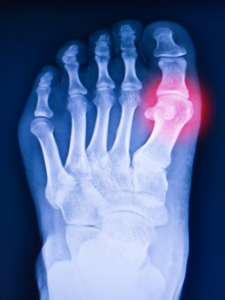

A 34-year-old man with chronic gout presented to the emergency room after sustaining trauma to his left foot. Diabetes and chronic alcoholism are in his past medical history. BMI was 26 kg/m2, blood pressure was 130/80 mm Hg blood pressure, and pulse was 84/min. His recent uric acid level measured 9 mg/dL. Routine lab findings, like a complete blood count and a complete metabolic pane,l were normal. The given X-ray of a patient with chronic gout shows Martel’s sign (Figure 1). Podagra is the inflammation of the base of the great toe (metatarsophalangeal joint) during gout flares. It is not a radiological sign. Chopart’s fracture and March fracture are also observed. Chopart’s fracture is a fracture between the talonavicular and calcaneocuboid joints. A March fracture is a fractured neck of the 2nd or 3rd metatarsal.

Figure 1: Foot X-ray with Martel’s sign